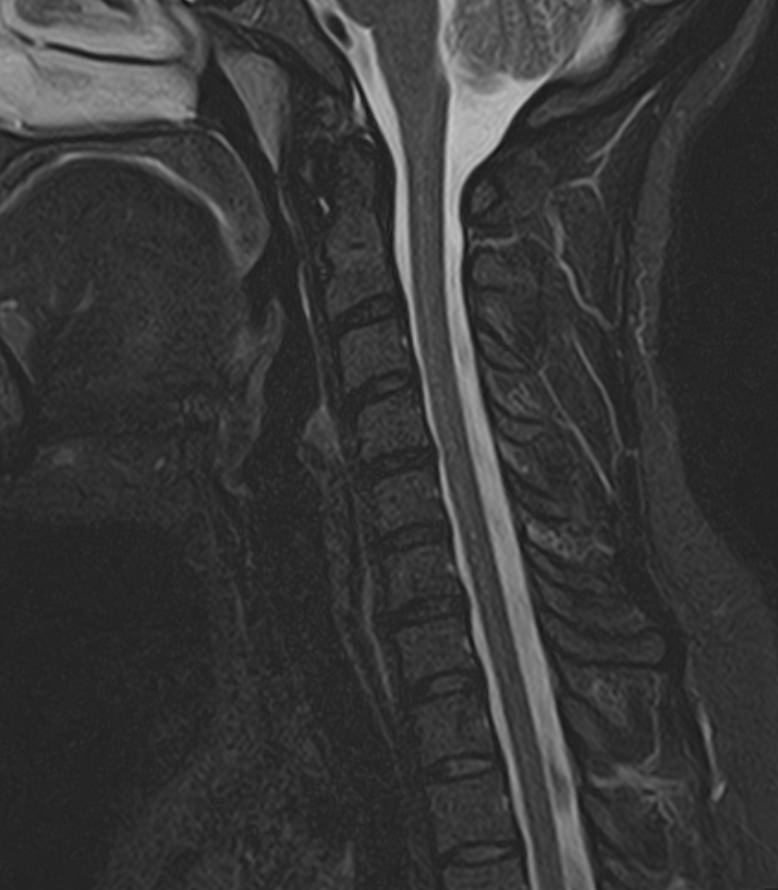

Шейный отдел позвоночника — это самый подвижный сегмент позвоночного столба, который испытывает повышенные нагрузки, подвержен травмам и развитию различных заболеваний. В эту анатомическую область входит 7 верхних позвонков, спинной мозг с отходящими от него нервными корешками, а также проходят крупные сосуды, кровоснабжающие головной мозг.

МРТ шейного отдела позвоночника позволяет проводить диагностику дегенеративных заболеваний позвоночного столба (в том числе межпозвонковых грыж, протрузий, остеохондроза), выявлять воспалительные, травматические изменения и объемные образования в области шейных позвонков и спинного мозга.

В клинике «Доступная медицина» данное исследование проводится на современном высокопольном магнитно-резонансном томографе экспертного класса TOSHIBA VANTAGE TITAN 1,5 Тесла. Напряженность магнитного поля 1,5 Тесла обеспечивает высокую разрешающую способность аппарата, что позволяет выявлять минимальные изменения в тканях и диагностировать заболевания на начальной стадии.

В большинстве случаев проводится стандартная магнитно-резонансная томография шейного отдела позвоночника без использования контраста, однако в некоторых случаях требуется контрастное усиление для детализации патологических очагов. Для этого применяется безопасное контрастное вещество на основе гадолиния (элемент, относящийся к редкоземельным металлам), которое полностью выводится из организма в течение суток преимущественно почками.